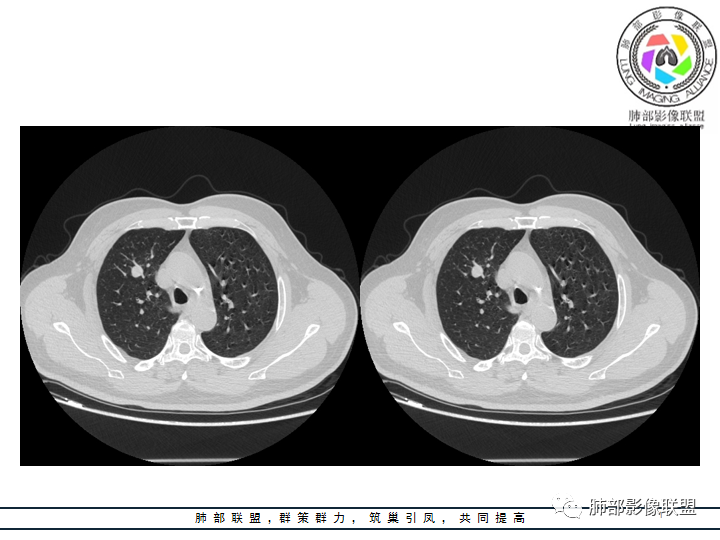

影像资料

老年男性患者,长期吸烟史,没有呼吸系统临床表现。胸部CT示右肺上叶实性密度结节影,密度均匀,未见空洞及钙化,边缘较光整,未见分叶及毛刺。血管影旁现侧出,支气管进入并截断,不均匀强化。

边缘光整,干净游离,密度均匀,没有钙化及空洞,没有卫星灶,PPD皮试(-)等,不符合结核球。